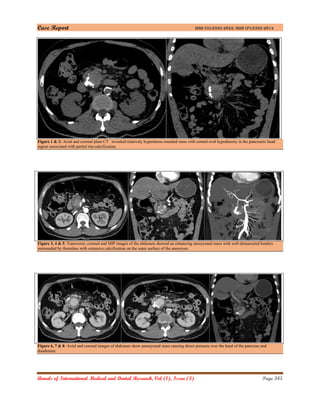

Axial and reconstructed coronal plain CT acquired on

a Philips 256 Slice iCT scanner revealed relatively

hyperdense rounded mass with central oval

hypodensity in the pancreatic head region associated

with partial rim calcification [Figure 1&2].

Dynamic axial and reconstructed coronal CT of the

abdomen performed with intravenous contrast

material in arterial phase showed an enhancing

aneurysmal mass with well-demarcated borders

surrounded by low-density areas, which was in

accordance with a thrombus with extensive

calcification on the outer surface of the aneurysm

[Figure 3,4 & 5]. The 48×44 mm aneurysmal mass

produced direct pressure over the head of the

pancreas and duodenum (Figure 6,7 & 8].

Figure 1 & 2: Axial and coronal plain CT revealed relatively hyperdense rounded mass with central oval hypodensity in the pancreatic head

region associated with partial rim calcification.

Figure 3, 4 & 5: Transverse, coronal and MIP images of the abdomen showed an enhancing aneurysmal mass with well-demarcated borders

surrounded by thrombus with extensive calcification on the outer surface of the aneurysm.

Figure 6, 7 & 8: Axial and coronal images of abdomen show aneurysmal mass causing direct pressure over the head of the pancreas and

duodenum.